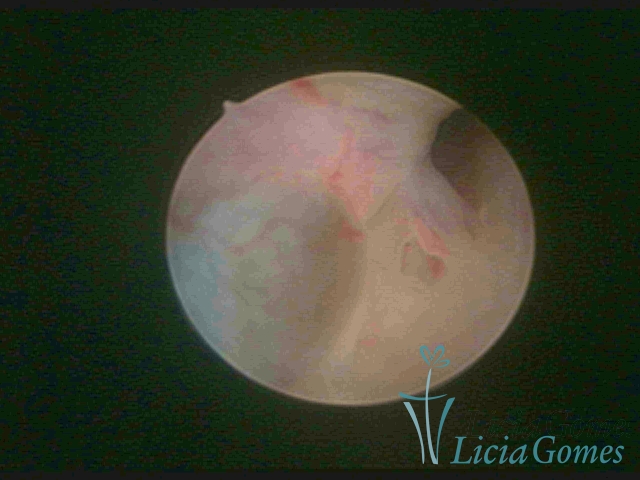

SINÉQUIA TIPO MUCOSA

As Sinéquia uterinas são cicatrizes (aderências) entre as superfícies das paredes uterinas, que podem ocorrer após manipulação cirúrgica, ou curetagem uterina, ou após um processo inflamatório na cavidade uterina (endometrite), podendo levar a alterações menstruais, infertilidade, e complicações obstétricas, como abortamento, parto prematuro.